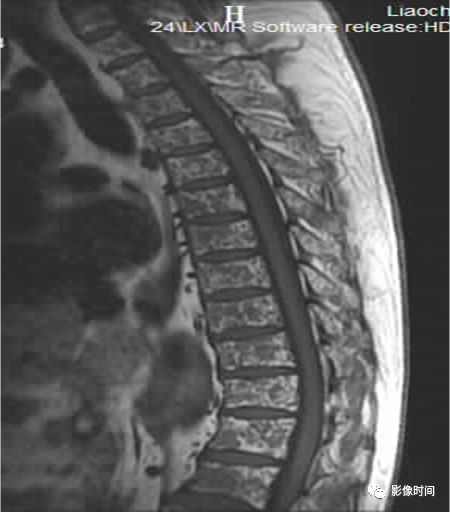

8牙膏征

牙膏征(Toothpaste sign)

牙膏征是指在矢状位脊柱影像中,脱出的椎间盘突入椎管内并向下游走,形似被挤出的牙膏而得名。

典型病例

矢状位 T2WI 像示脱出的椎间盘突入椎管,形似被挤出的牙膏,呈牙膏征(箭示)。

引用自:https://radiopaedia.org/ articles/ toothpaste-sign